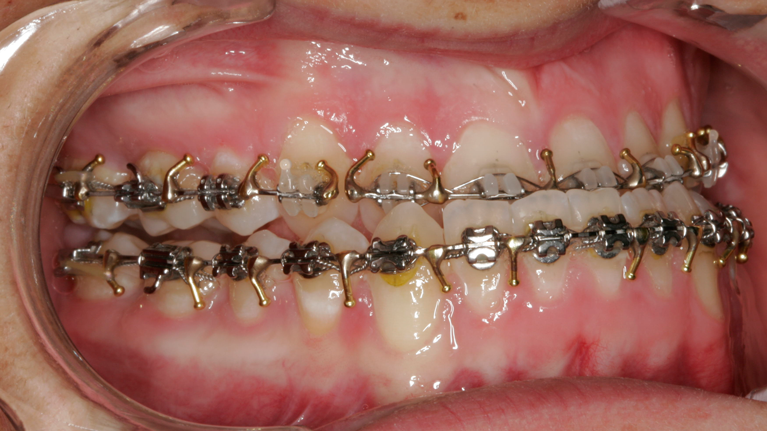

Til konferencen møder du en kirurgisk specialtandlæge fra Kæbekirurgisk Afdeling, muligvis en uddannelsestandlæge og en bøjletandlæge. De fremlægger den foreløbige behandlingsplan, som de forinden har udarbejdet. Du har mulighed for at få uddybet eventuelle spørgsmål til behandlingsplanen.